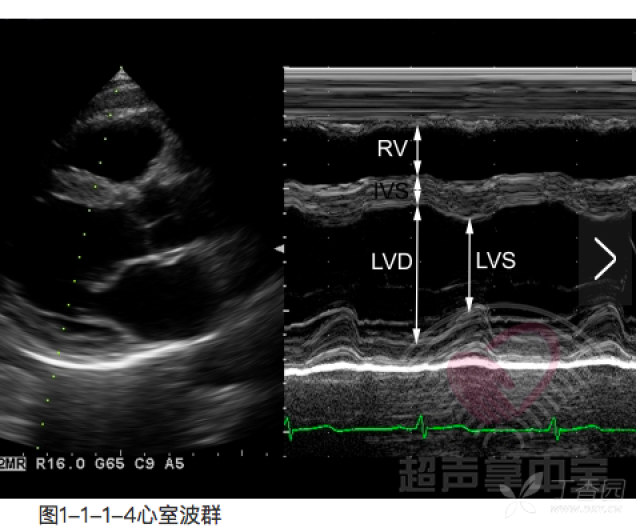

m型超声心动图入门

m型超声心动图解读

超声心动图解读